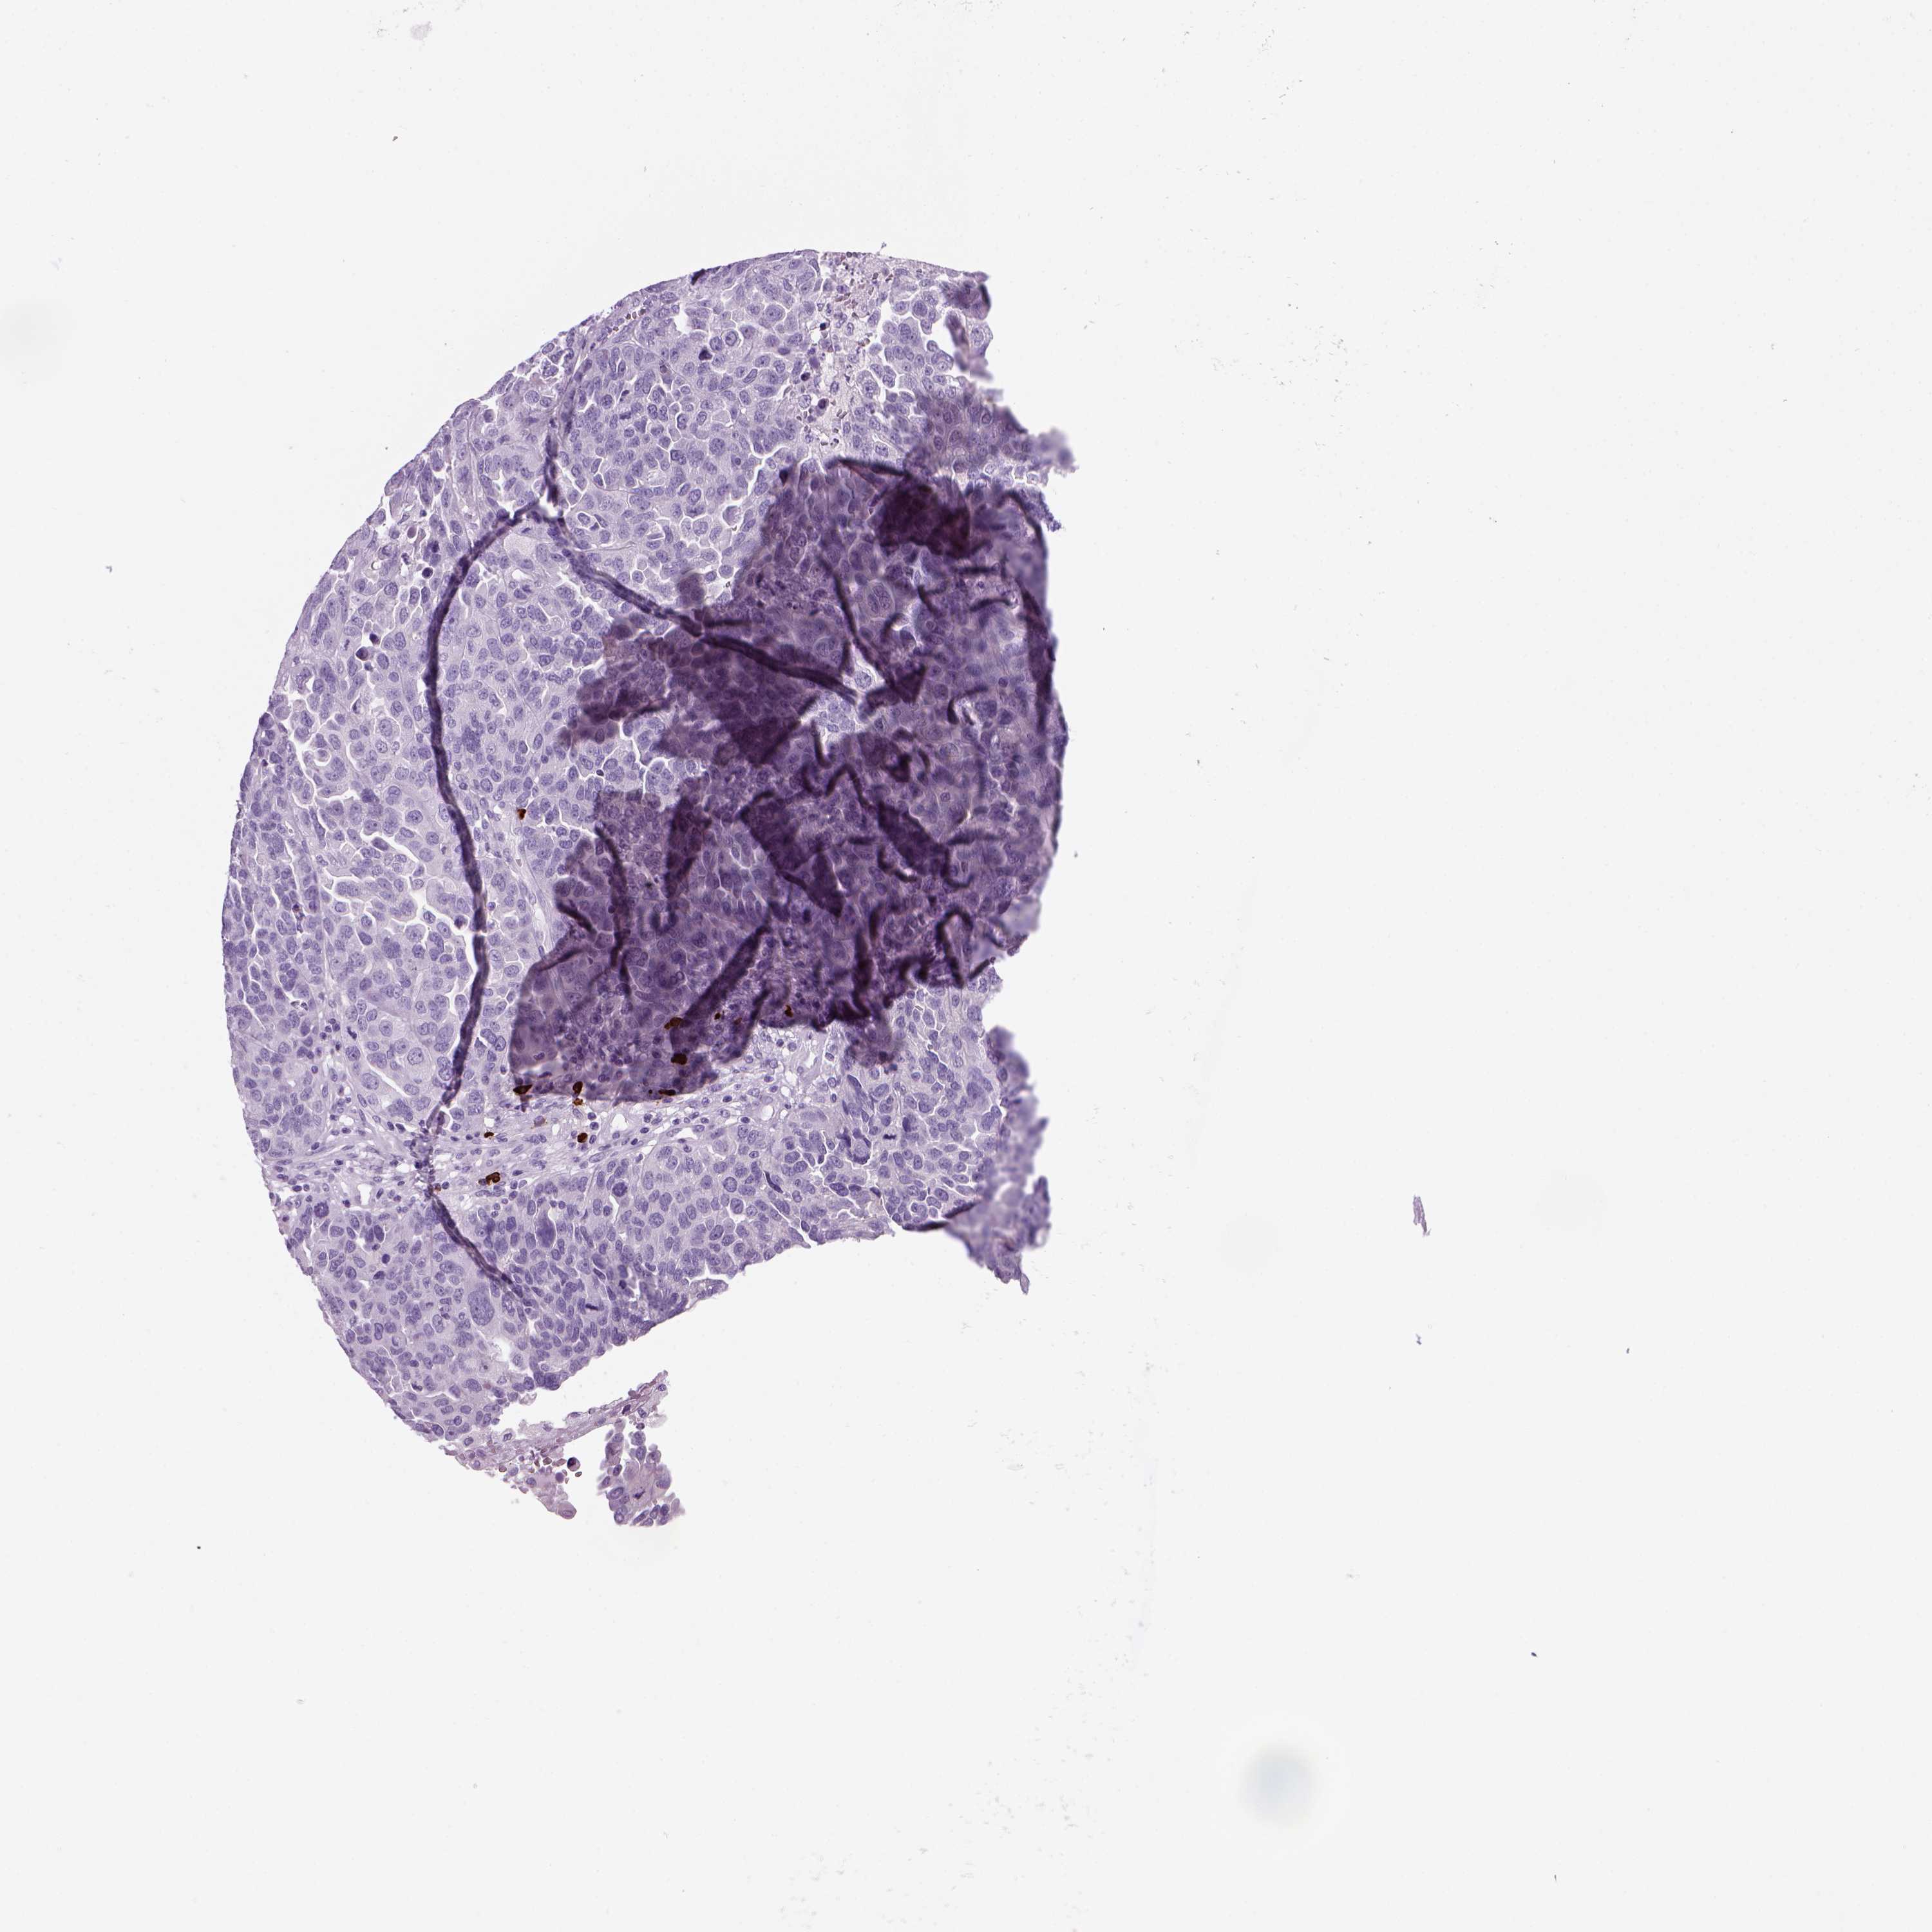

OVARIAN CANCER - Protein expressioni

A mouse-over function shows sample information and annotation data. Click on an image to view it in a full screen mode. Samples can be filtered based on level of antibody staining by selecting one or several of the following categories: high, medium, low and not detected. The assay and annotation is described here.

Note that samples used for immunohistochemistry by the Human Protein Atlas do not correspond to samples in the TCGA dataset.

Antibody stainingi

Antibody staining in the annotated cell types in the current human tissue is reported as not detected, low, medium, or high, based on conventional immunohistochemistry profiling in selected tissues. This score is based on the combination of the staining intensity and fraction of stained cells.

Each image is clickable and will lead to virtual microscopy that enables deeper exploration of all samples and also displays staining intensity scores, fraction scores and subcellular localization as well as patient and tissue information for each sample.

Antibody HPA043745

Antibody HPA052694

Cystadenocarcinoma, serous, NOS

Carcinoma, endometroid

Cystadenocarcinoma, mucinous, NOS

Carcinoma, NOS